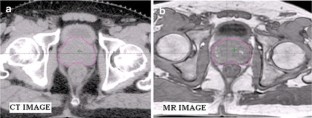

Fig. 1